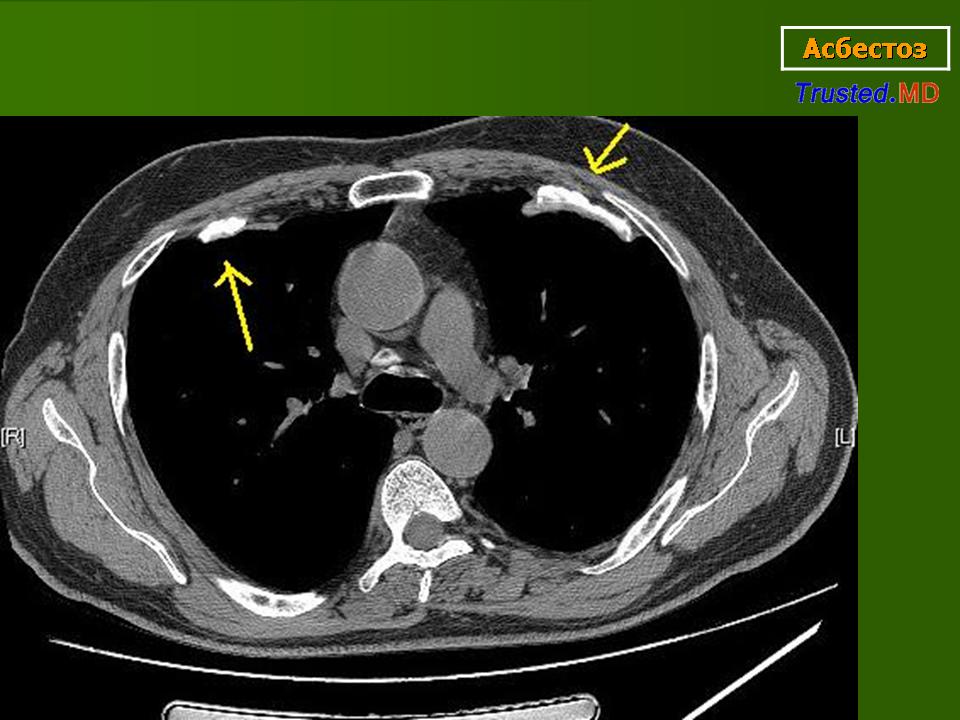

При развитии асбестоза на рентгенограмме можно увидеть неправильной формы или линейные очаговые тени. В начале такие изменения появляются в нижней трети легкого(их), когда заболевание начинает прогрессировать, то изменения определяются в верхней и средней третях. Если фиброз сильно выражен, то граница сердечной тени становится нечеткой или же возникают однородные ограниченные затемнения легочных полей. Нарастание фиброза влечет за собой формирование сотового легкого, имеющего классическую рентгенологическую картину, т. е. величины смешаны с мелкими полостями (их диаметр составляет, как правило, от 7 до 10 мм), видны очаговые тени разной формы, и облитерация целых ацинусов.

Рентгенологические признаки асбестоза I стадии: нерезкое усиление легочного рисунка за счет перибронхиального, пери-васкулярного и межуточного фиброза преимущественно в прикорневых и средних поясах легких, имеющего сетчатую и мелкопетлистую структуру, небольшие изменения плевры (утолщение, базальные спайки); корни легких несколько деформированы, уплотнены.

На рентгенограммах сосудисто-бронхиальный рисунок резко усилен, имеет более грубую сетчатую структуру. Иногда обнаруживаются немногочисленные мелкопятнистые тени узелкового характера. Прозрачность легочных полей повышена. Корни легких значительно уплотнены, расширены. Могут выявляться начальные признаки легочного сердца.